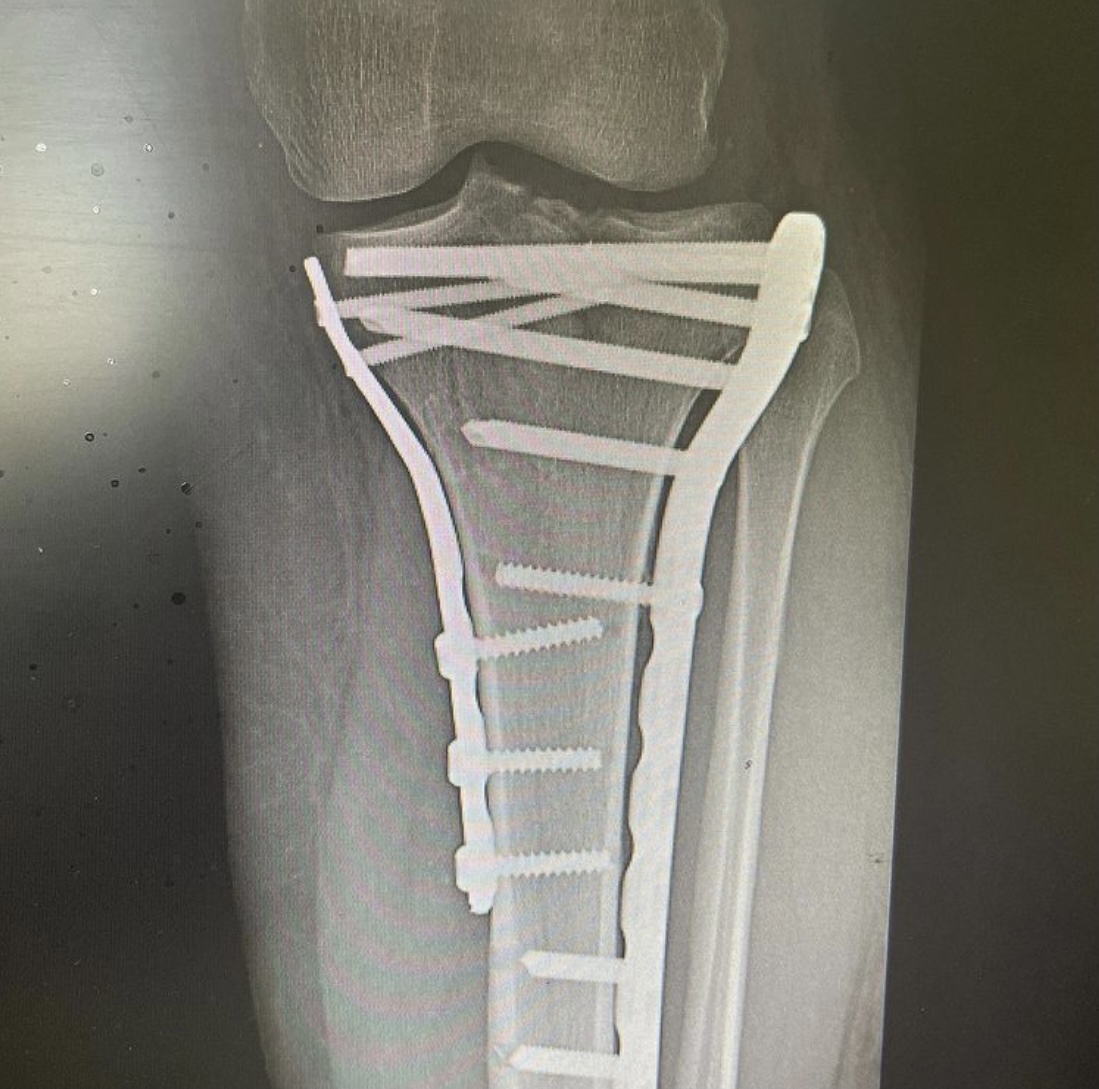

На операционном столе пациент с травмой в результате падения с самоката — многооскольчатый перелом верхнего суставного конца большеберцовой кости с разрывом боковых связок.

«Выполнен остеосинтез пластинами и винтами, восстановлены связки коленного сустава, — рассказывает хирург — травматолог ГКБ 7 Казани Руслан Ильгизарович Закиров. — Самокат в последнее время стал достаточно популярным средством попадания в травматологическое отделение нашей клиники. Большая скорость, маленькие колёса и неровности на дороге, необходимость объезжать пешеходов на тротуаре…. все это пополняет печальную статистику дорожно — транспортных происшествий».